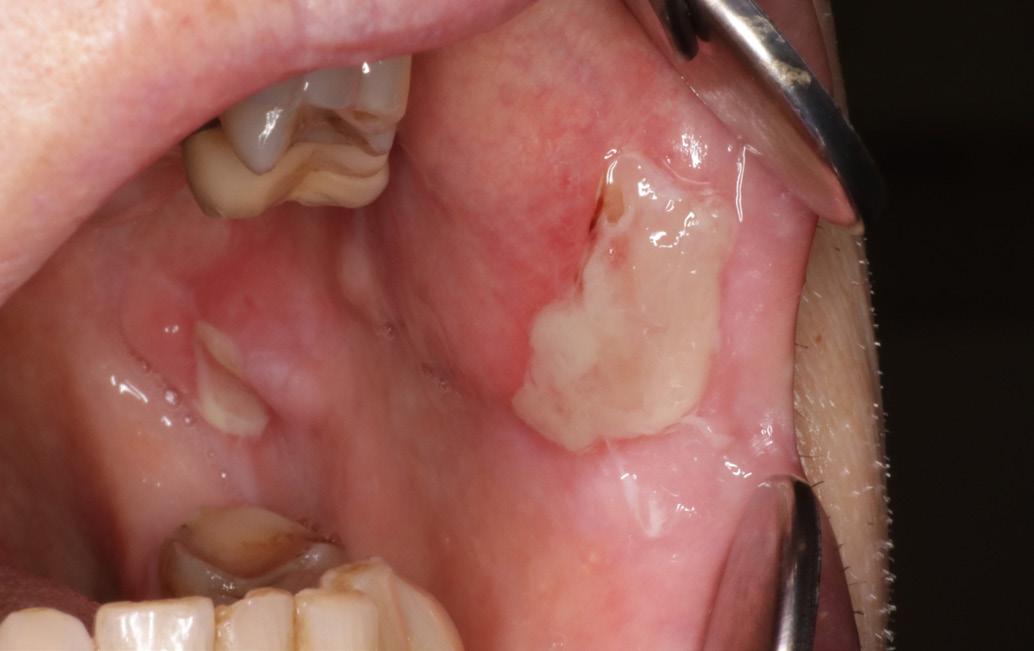

Case 2

An 80-year-old female presented to the Oral Medicine Clinic with painful oral ulcers that had been present since June 2025. She had been taking 15 mg methotrexate along with folic acid supplementation.

Oral examination revealed multiple ulcerations on the tongue (Fig. 2 a) and buccal mucosa. Initial management with dexamethasone and chlorhexidine mouthwash provided no improvement. A swab of the lesions showed moderate growth of fungus, and Amphotericin lozenges was prescribed, but this also had no effect.

The patient’s general practitioner was consulted, and methotrexate was suspended for three weeks. Following this, resolution of the ulcers was noted (Fig. 2b). She was then prescribed dexamethasone mouthwash, which led to marked improvement of the lesions.

Fig. 2 A

Multiple painful ulcers on the tongue and buccal mucosa in an 80-year-old female taking methotrexate and folic acid, resistant to initial topical therapy and antifungal treatment.

2 B

Fig.